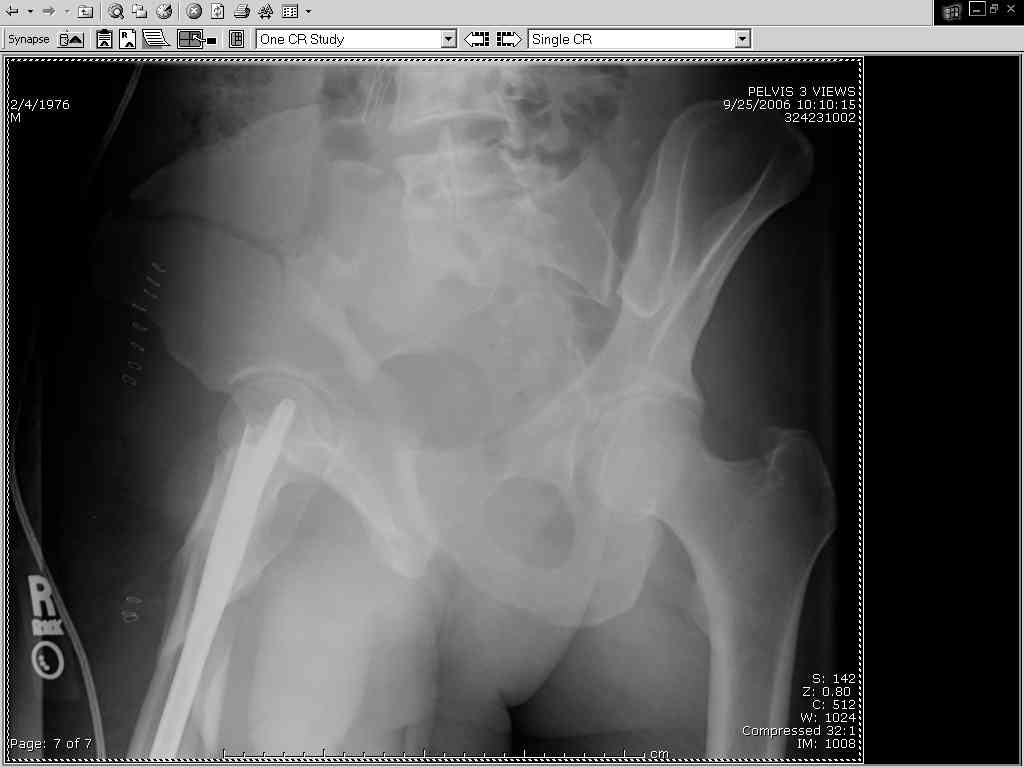

Thanks Adam - I agree it's not a pure APC (is there really such thing as a pure force vector strictly in the x,y or z plane?). I stand corrected. Maybe a hybrid APC (ext rot of L hemipelvis, symphysis disruption, ext rot of R anterior innominate) plus vertical shear as well with 3 or-so cm of cephalad migration of the R ilium. Maybe just "C-type".....

My current plan is supine, ORIF symphysis with as close to AFT reduction as possible, then fix the R ilium via lat window Ilioing.

approach with lags in the solid crest bone, 2 plates (one along pelvic brim and one up on the inside of the crest), then, if I have good posterior reduction and can get a good view of the ICD on my lat sacral view with image, L side perc SI screw, if not then anterior L SI approach and 2 anterior plates.

It almost looks to me like an extra-articular both column fx, in addition to the pelvic component. It has the typical triangular fragment and the OO view has a hint of the spur. You may be able to get it all with plates. I would consider fixing the crest first, then a long plate for both symph and iliac portion. SI may close with reduction of symphisis. Looks like the inferior portions are intact. I like your plan as well. You will probably solicit lots of opinion. Good luck. Look forward to post op view.